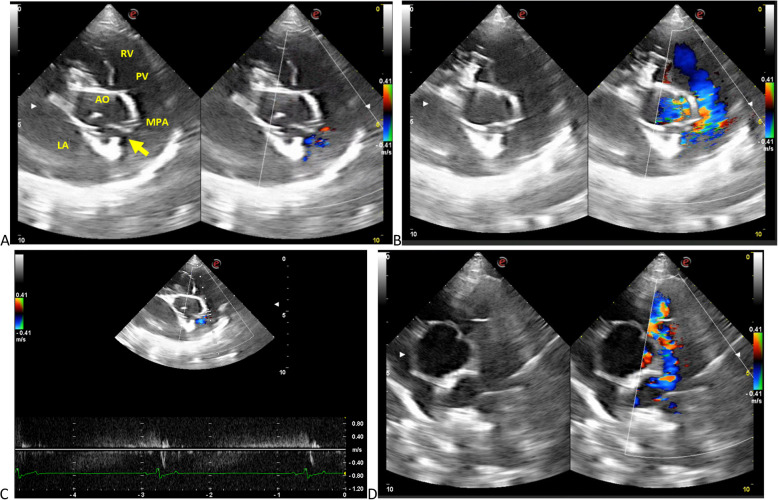

在麻醉前超声心动图评估中,一只3岁雌性塔特兰猎犬偶然诊断出左冠状动脉和肺动脉主动脉之间的血管通信(冠状动脉瘘)。考虑到患者的病史、临床检查和诊断成像,没有怀疑创伤和心内膜炎,这可能是导致这种疾病发展的原因。经胸超声心动图示左冠状动脉开口扩张,彩色及频谱多普勒示持续分流,诊断为冠状动脉瘘。通过计算机断层扫描证实了这一诊断。冠状动脉瘘在人类和动物中都是罕见的发现。据作者介绍,这是第一例犬左冠状动脉和肺动脉主动脉之间先天性瘘的临床报道。

A vascular communication between the left coronary artery and the main pulmonary artery (coronary fistula) was incidentally diagnosed in a 3-year-old female Tatran hound during a pre-anesthetic evaluation using echocardiography. Trauma and endocarditis were not suspected given the patient's history, clinical examination, and diagnostic imaging, which could have contributed to the development of this condition. Transthoracic echocardiography revealed dilation of the left coronary ostium, and continuous shunting on color and spectral Doppler was observed and this led to the diagnosis of coronary artery fistula. This diagnosis was confirmed through computed tomography. Coronary artery fistulas are infrequent findings in both humans and animals. According to the authors, this is the first reported clinical case of a congenital fistula between the left coronary artery and the main pulmonary artery in a dog.